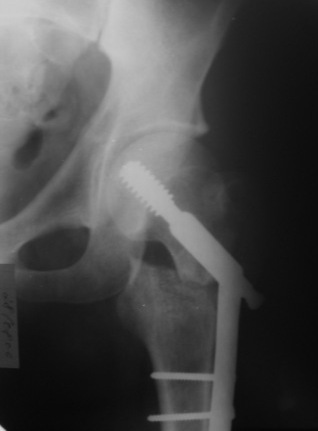

К сожалению под рукой только одна картинка от этой операции.

Я пошел на операцию имея стерильным и обычный бедренный гвоздь ChM и реконструктивный.

Когда открыто убрали DHS встали перед выбором, что ставить? Так, как это был подвертельный перелом - поперечная линия на уровне малого вертела то поставили обычный бедренный гвозь и один прокс блокирующий винт, который затянули компрессирующей заглушкой.